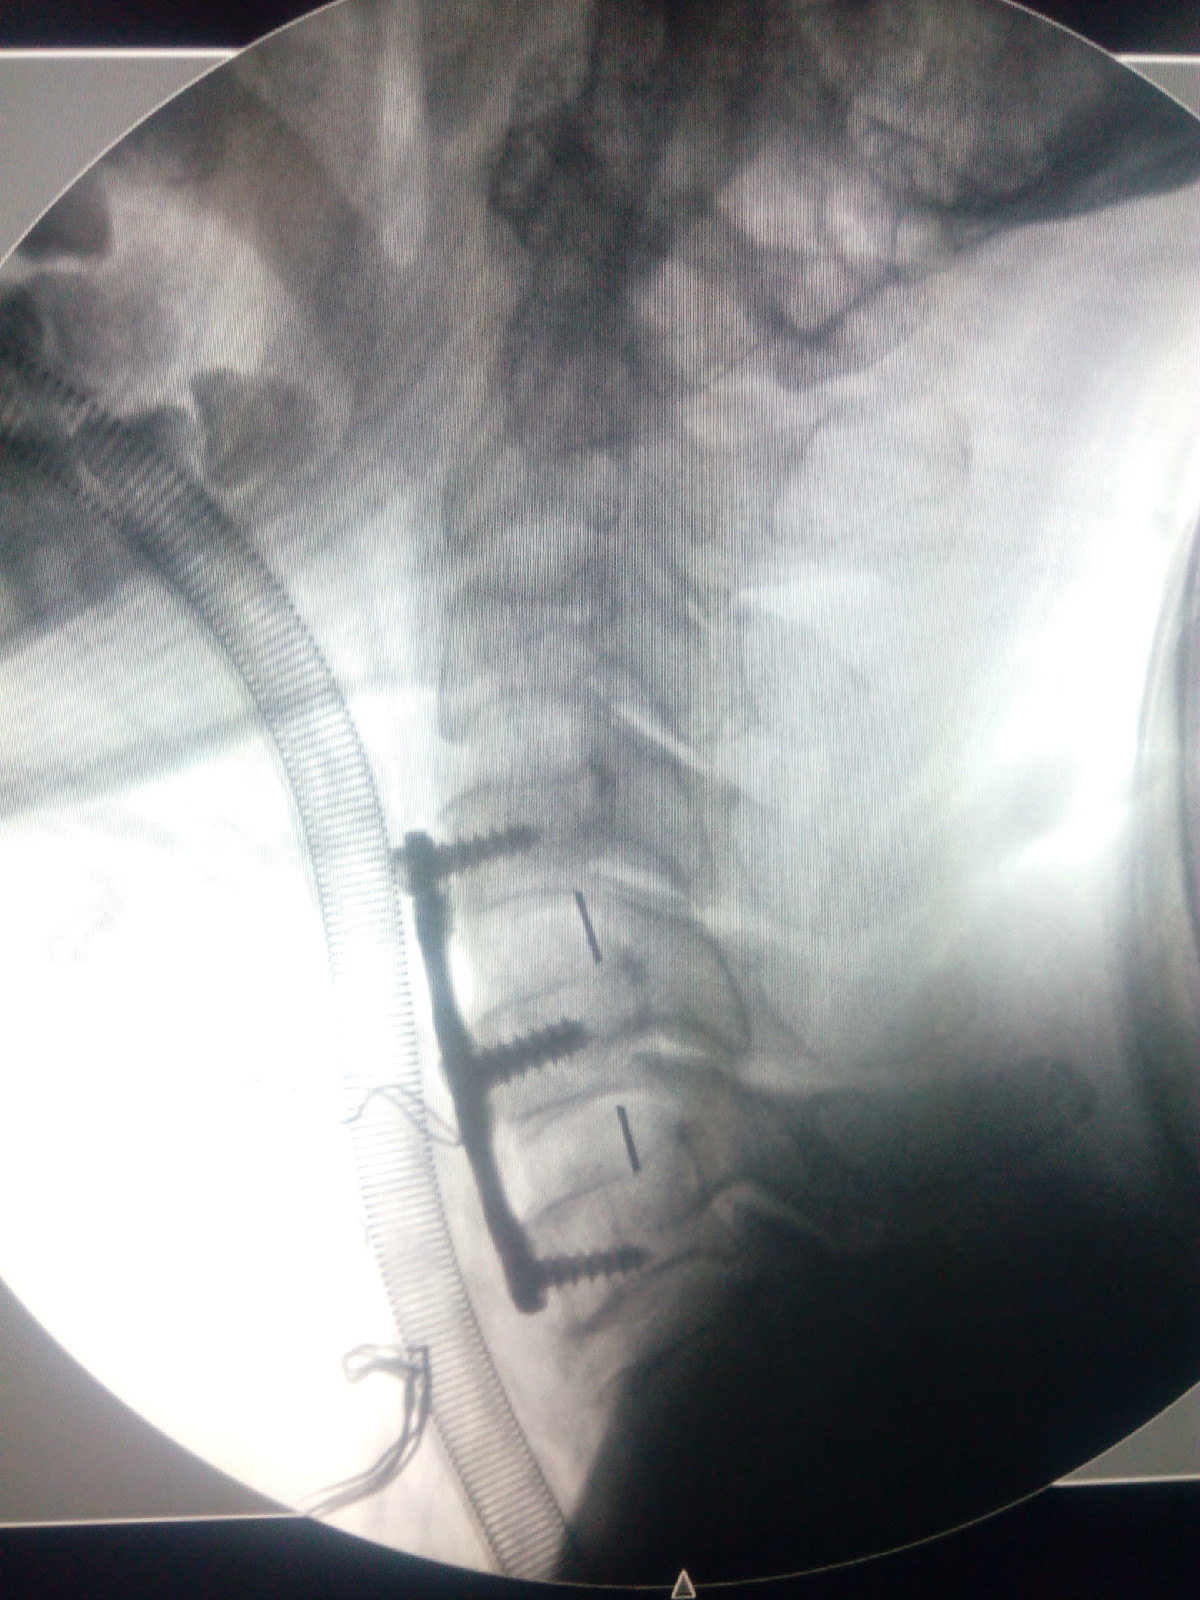

病例3-脊髓型颈椎病-颈椎前路减压固定融合术

1200x1600 - 391KB - JPEG